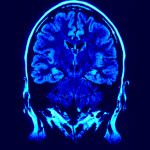

In più, va notato come in entrambi gli studi, l’utilizzo del composto abbia ridotto in maniera significativa le lesioni celebrali attive (osservate tramite risonanza magnetica).